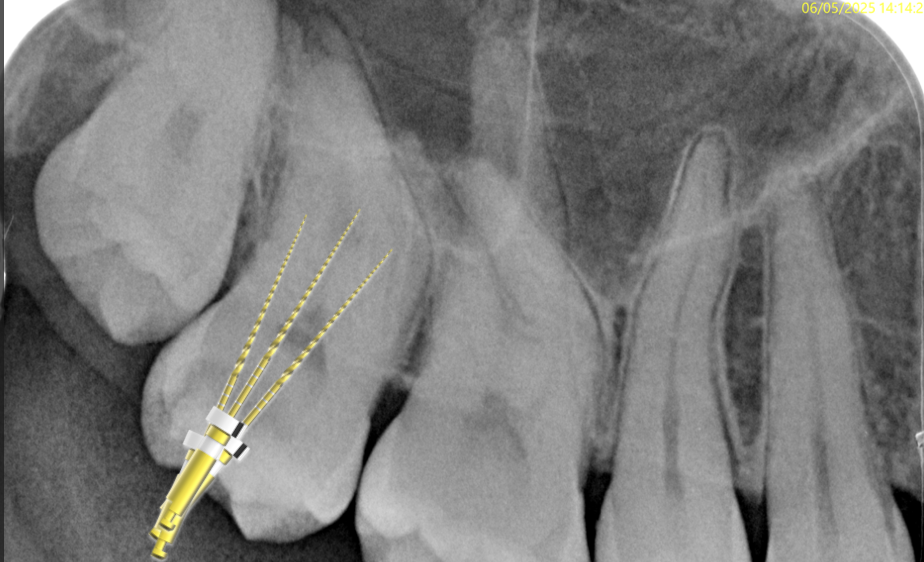

Fig. 8

After pre flaring, I was able to reach the working length in all the root canals with the R1 file.